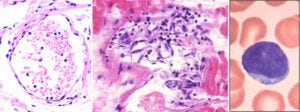

We now turn to the evidence of immune attack on the endothelial cells which produce the spike protein. On the left, a normal venule, delimited by an intact endothelium and containing some red blood cells and few white blood cells (stained blue) inside.

The image on at the centre shows a venule that is being attacked and destroyed by the immune system. The outline is already dissolving, and the spindle-shaped (and swollen) endothelial cells have peeled off from the vessel wall. Furthermore, we see lymphocytes—the small cells with dark, round nuclei and with very little cytoplasm around them; a single lymphocyte (at much higher magnification) is shown on the right.

Lymphocytes are the backbone of the specific immune system—whenever antigens are recognized and antibodies are produced, this is done by lymphocytes. Also among the lymphocytes we find cytotoxic T cells and natural killer cells, which serve to kill virus-infected cells—or ones that look to them as if infected, because they have been forced to produce a viral protein by a so-called vaccine.

11. Healthy heart muscle tissue, and lymphocytic myocarditis

In Slide 7, we saw that heart muscle cells strongly expressed the spike protein after vaccine injection. Here, we see the consequences. The picture on the shows a sample of healthy heart muscle tissue, with regularly oriented and aligned heart muscle fibres. On the right, we see a heart muscle sample from one of the autopsies. The muscle fibres are disjointed and disintegrating, and they are surrounded by invading lymphocytes. Burkhardt found myocarditis in multiple of his deceased patients.